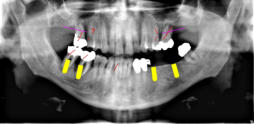

Beispiele für komplexe implantologische Versorgungen aus unserer Gemeinschaftspraxis

(Planung / Endversorgung -- als Röntgenaufnahmen)

C1

C2

C3